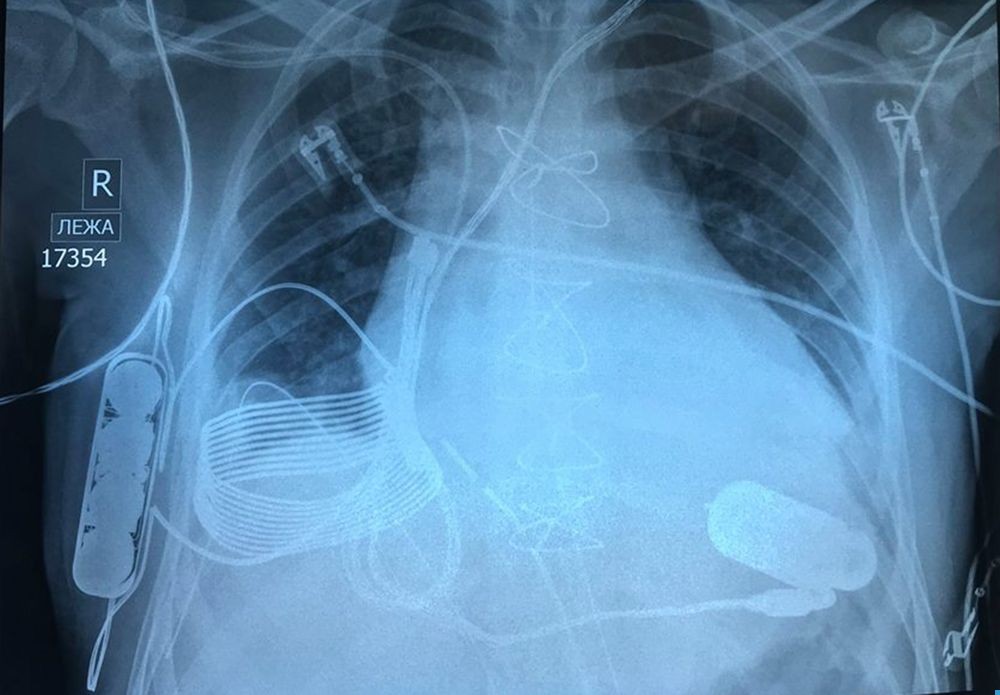

24х-летнему Исмаилу Урсунову, жителю Казахстана, диагностировали сердечную недостаточность последней стадии. Ему требовалась пересадка сердца, однако сделать пересадку в ближайшее время не представлялось возможным. Исмаил Урсунов решился испытать на себе новейшую разработку израильских медиков и пошел на риск, несмотря на то, что такие оперативные вмешательства не проводили ранее никому. Хирурги ему вживили специальный имплантат – вспомогательное устройство левого желудочка сердца. Именно это механическое устройство помогает его сердцу перекачивать кровь.

Особенностью данного механизма является возможность его зарядки без проводов. А это значит, что миллионы жизней людей могут быть спасены. К тому же в данном случае, как утверждают специалисты, исключается возможность инфицирования.

Эта новейшая технология обеспечила возможность зарядки без обязательного присутствия электросетей. Специальный пояс, который надевает человек с внедренным «бионическим» сердцем, даёт возможность зарядить устройство беспроводным способом.

Уникальную технологию механической беспроводной поддержки сердца разработали израильские специалисты. Ученые из фирмы Leviticus Cardio. усердно трудились над изобретением более 10 лет, они и стали соавторами проекта, изготовив устройство для беспроводной зарядки насоса. Конструкторы Leviticus Cardio разработали систему, синхронизировав детали, имплантированные внутрь тела пациента, и наружные составляющие. После подзарядки устройство функционирует восемь часов, затем требуется новая порция энергии. Чтобы произвести следующую зарядку, нужно надеть жилет, в который вмонтирована внешняя катушка. Она разыскивает катушку внутреннюю и производит зарядку методом электромагнетизма.